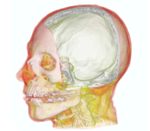

Morphing and warping. Part I. Halazonetis DJ. Am J Orthod Dentofacial Orthop. 1999 Apr;115(4):466-77. doi: 10.1016/s0889-5406(99)70074-0. PMID: 10194292